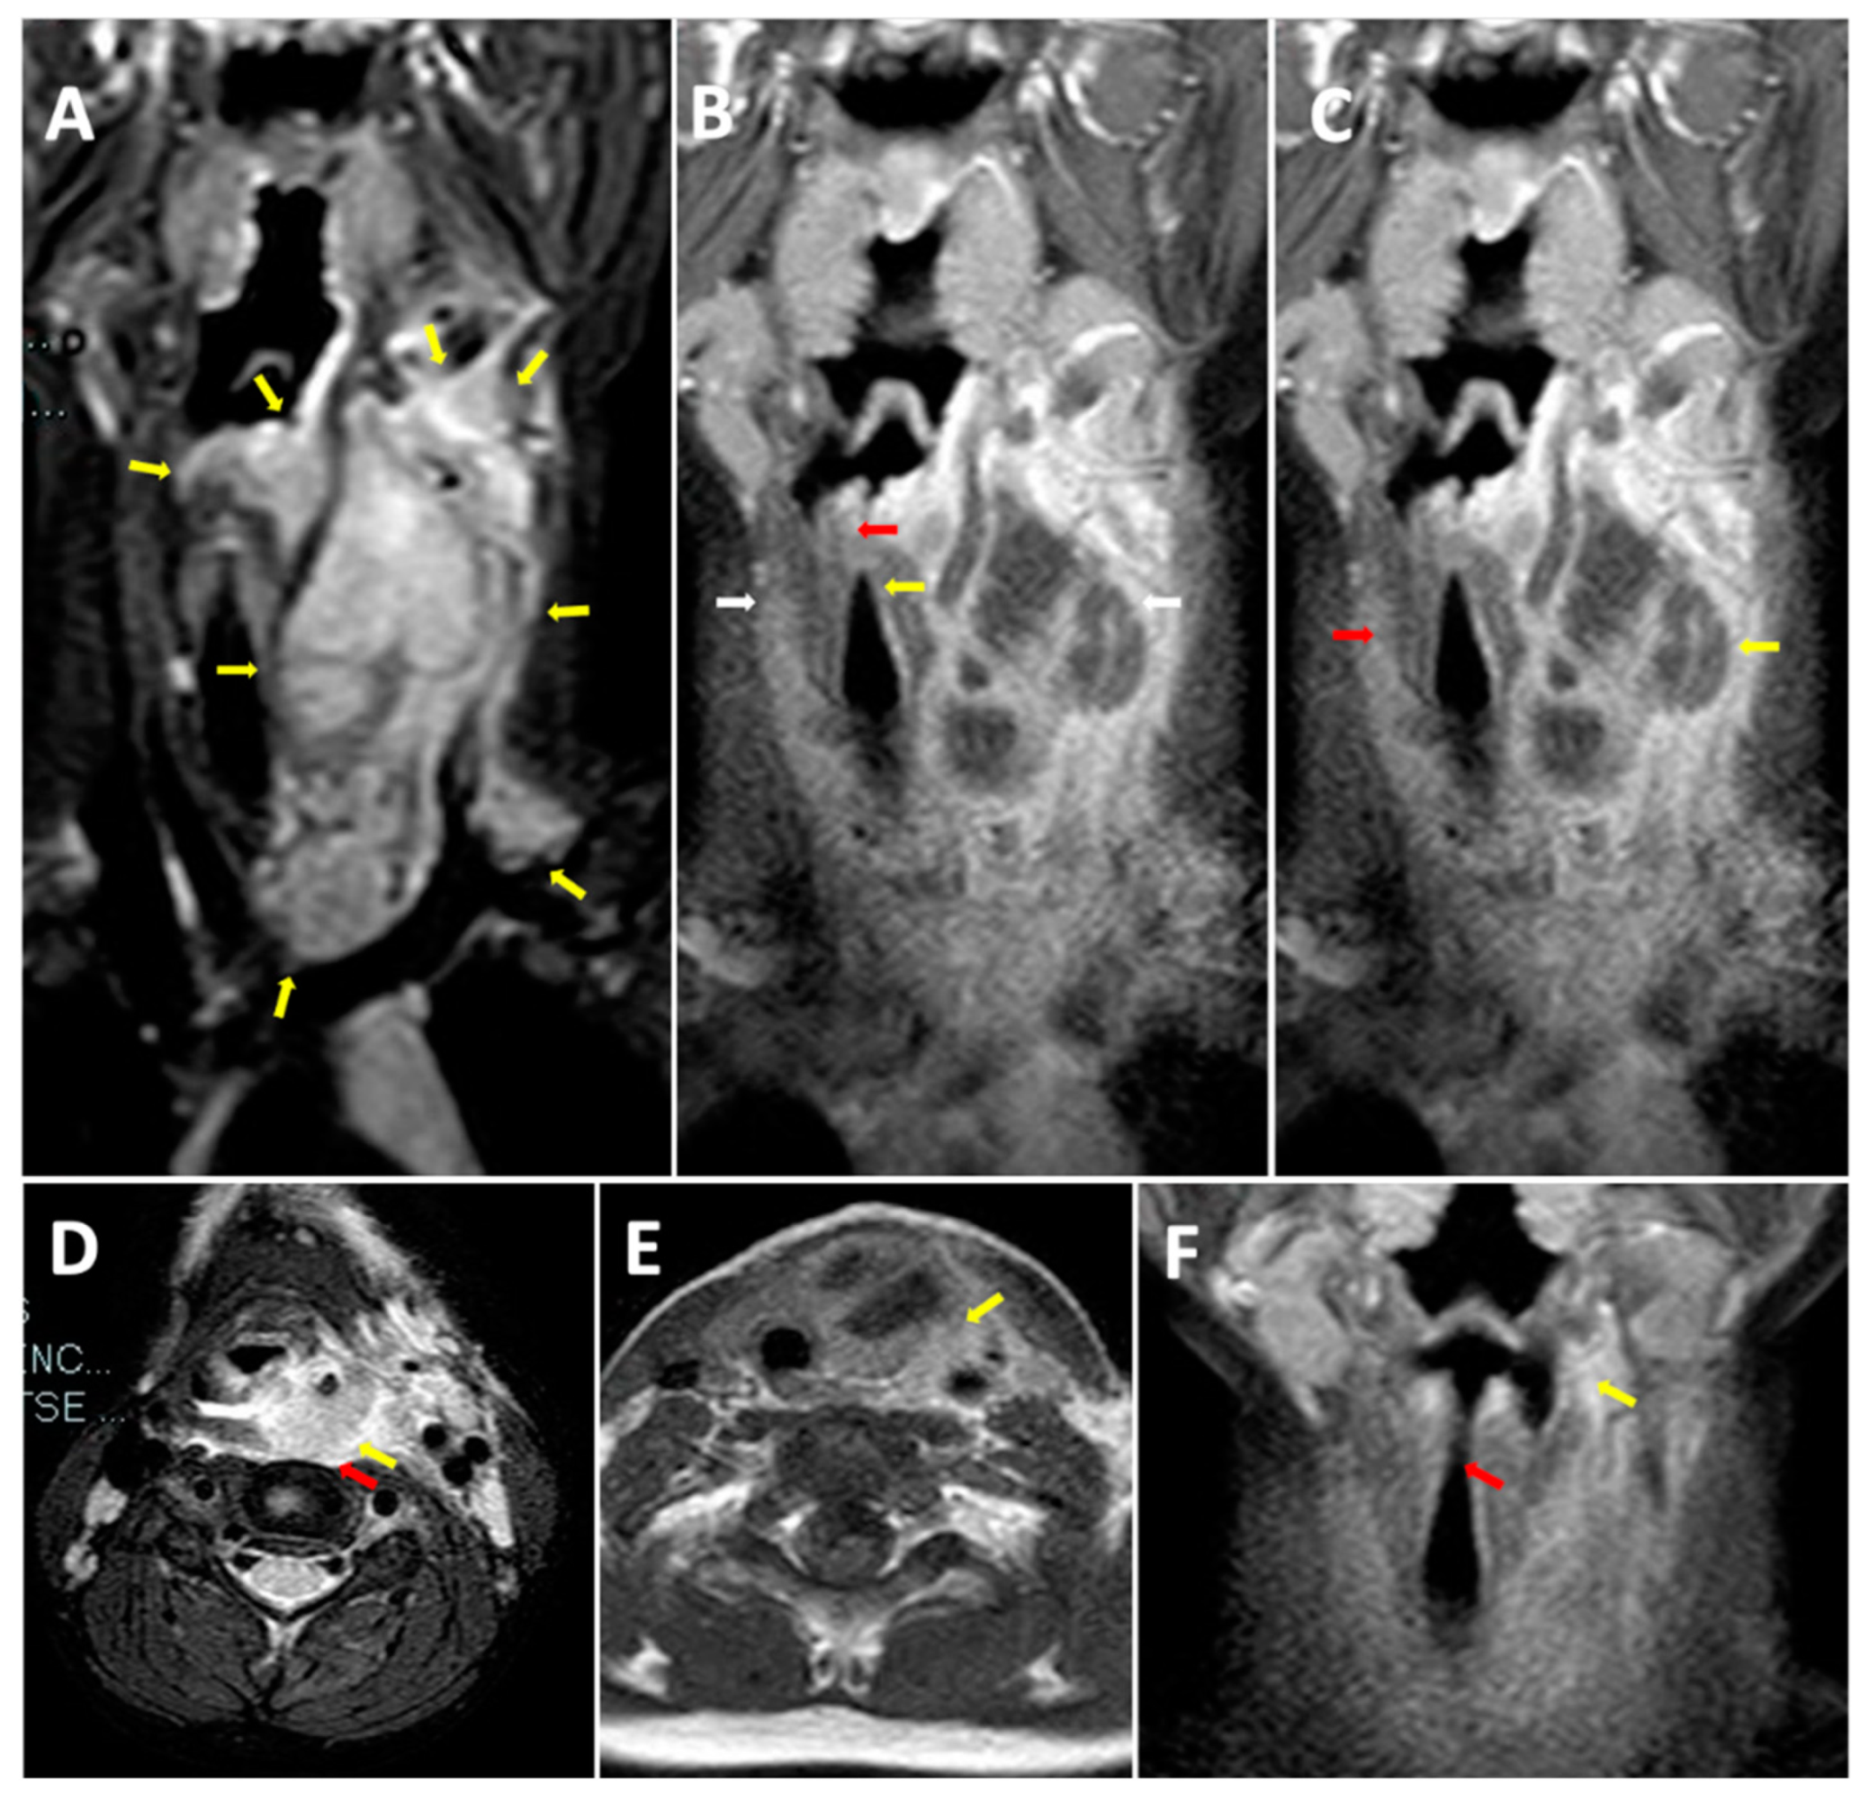

2. Case Report

2.2. Investigations for Recurrent Neck Abscesses